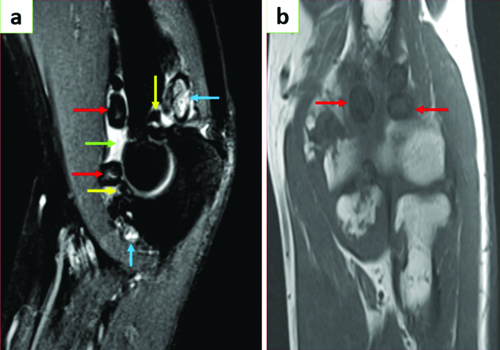

MRI of the elbow joint [Table/Fig-3a,b] shows T2 hyperintense joint effusion with multiple T1 and T2 low signal extra- and intra-articular loose bodies in the elbow joint. A few T2 hyperintense loose bodies are noted due to a lack of mineralisation. The ligaments around the elbow joint appear intact, and there is no evidence of bone marrow oedema or significant soft tissue swelling.

MRI of the elbow joint: a) Sagittal T2 and; b) Coronal T1 sections of elbow joint showing multiple ossified extra-articular (red arrows) and intra-articular (yellow arrows) loose bodies with central hyperintensity in T2WI. Few non-ossified T2 hyperintense loose bodies noted (blue arrows). Joint effusion is seen (green arrow).